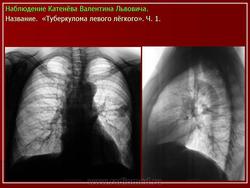

Рис. 1А,Б,В.

Во втором сегменте верхней доли левого легкого фокус уплотнения с мелкобугристой поверхностью, нечеткими контурами. По периферии видны короткие и длинные тяжи переходящие в прилежащие отделы легочной ткани. Отмечается усиление легочного рисунка в окружающих отделах, видны мелкие очаги с нечеткими контурами. В средостении единичные увеличенные до 1, 2 см лимфатические узлы в некоторых из них определяются известковой плотности включения.

Рис. 2А,Б,В. В сторону корня легкого тянется дорожка инфильтрации легочной ткани. У медиального края прослеживается просвет субсегментарного бронха, стенки которого ровные.

Рис. 3А,б. Верхним полюсом фокус уплотнения тесно прилежит к костальной плевре, последняя неравномерно утолщена.

В данном наблюдении обострение туберкулезного процесса произошло по инфильтративному типу. По сравнению с представленными снимками отмечено увеличение размера фокуса уплотнения на 0,4 см в течение последних 3 месяцев. Следует отметить, что увеличение размеров фокуса, появление нечеткости контуров при мелкобугристой поверхности напоминают картину периферического рака.

Важными дифференциально-диагностическими признаками, позволяющими исключить опухолевую природу, являются: единичные очаги в окружающей легочной ткани на фоне усиленного легочного рисунка, наличие длинных тяжей по контуру образования, дорожка к корню легкого и неравномерное утолщение прилежащих отделов плевры.